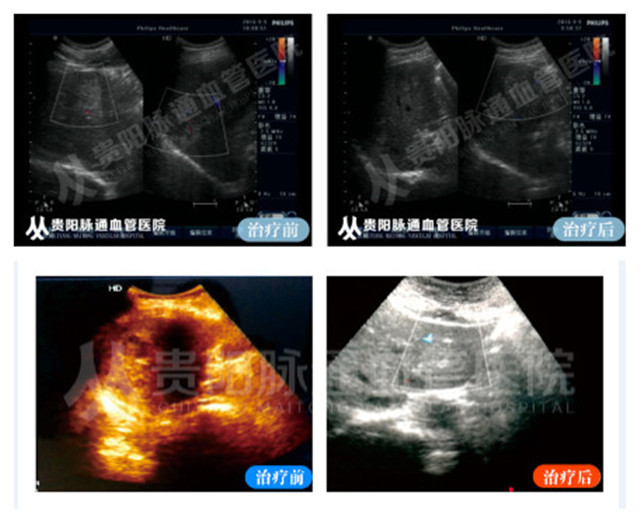

案例分享:

安順醫(yī)院治療肝血管瘤哪家好,安順肝血管瘤哪家醫(yī)院好